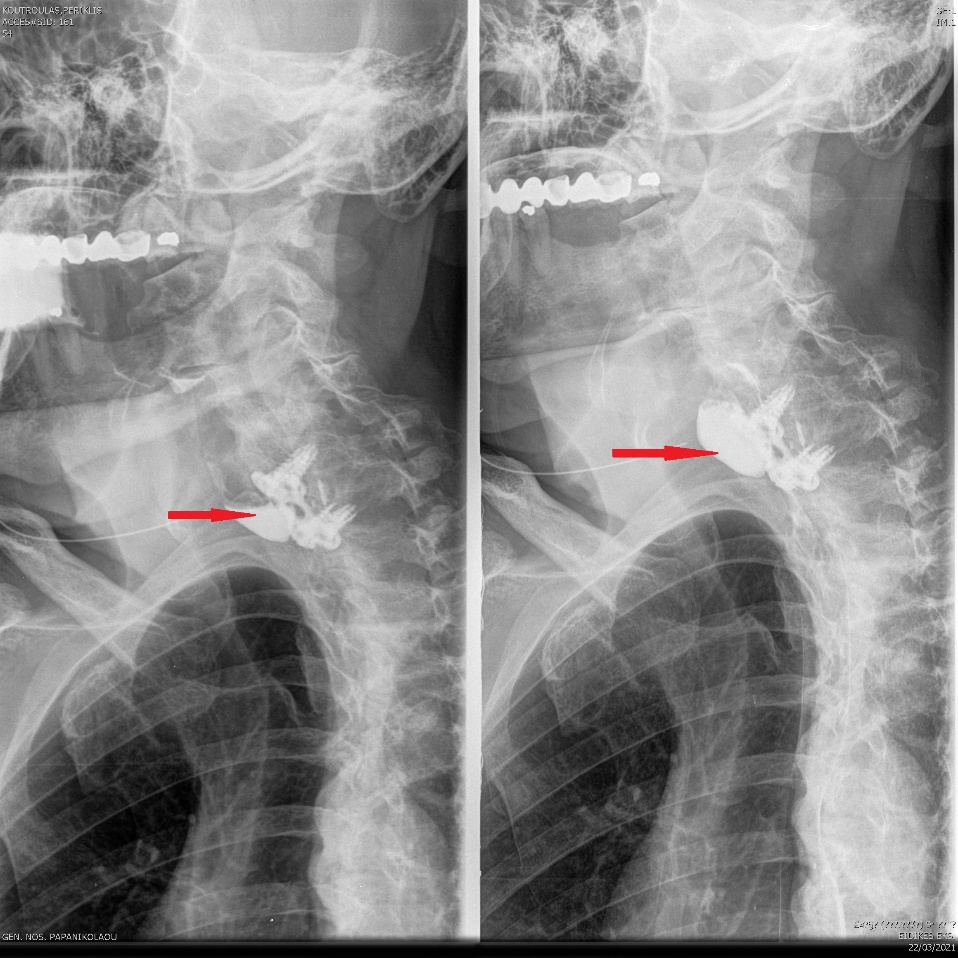

Esophagography. Arrows demonstrate a small posterior pseudodiverticulum of the esophagus adjacent to the metallic plate and screws (Courtesy Dr. V. Penopoulos)